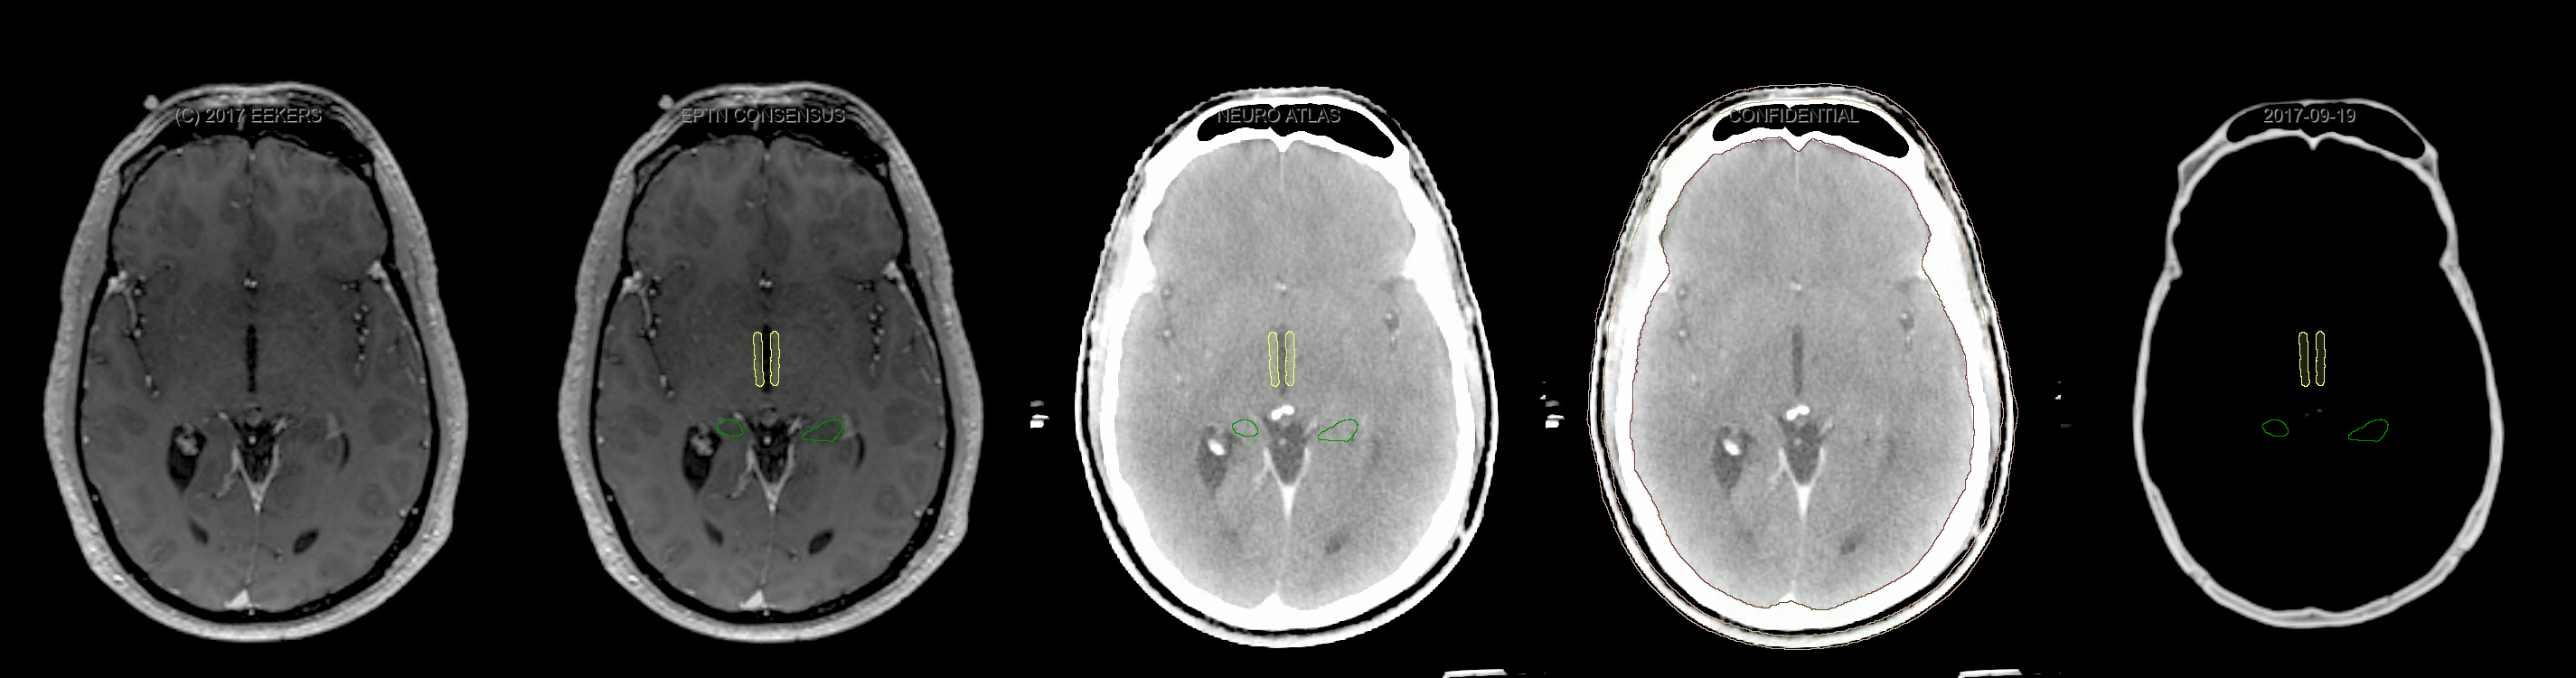

Eekers et al. have published an international neurological atlas for contouring of organs at risk in consensus with the European Particle Therapy Network (EPTN). The purpose of this consensus atlas is to decrease inter- and intra-observer variability in delineating OARs relevant for neuro-oncology. We propose this atlas is used in photon and particle therapy in order to derive consistent dosimetric data. When required this atlas will be updated according to new insights.

Included are all OARs known to be relevant for radiation-induced toxicity in neuro-oncology: brain, brainstem, cochlea, vestibulum & semicircular canals, cornea, lens, retina, lacrimal gland, optic nerve, chiasm, pituitary, hippocampus and skin. A new OAR relevant for neuro-cognition, the posterior cerebellum is also included.

Three-dimensional delineation of the fifteen consensus OARs for neuro-oncology are shown on CT and 3 Tesla (3T) MR images (slice thickness 1 mm with intravenous contrast agent). All are presented in transversal, sagittal and coronal view.

From left to right: MR without structures, MR with structures, CT (WW/WL 120/40) with structures, CT (WW/WL 120/40) with Brain and Brainstem Surface, CT (WW/WL 1500/120)with structures